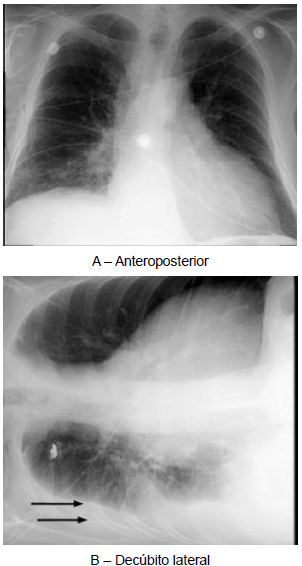

Pneumologia

As radiografias acima foram realizadas em paciente com história de trauma torácico, cujo diagnóstico clínico-radiológico é

A

atelectasia pulmonar.

B

infarto pulmonar.

C

pneumonia.

D

derrame pleural.